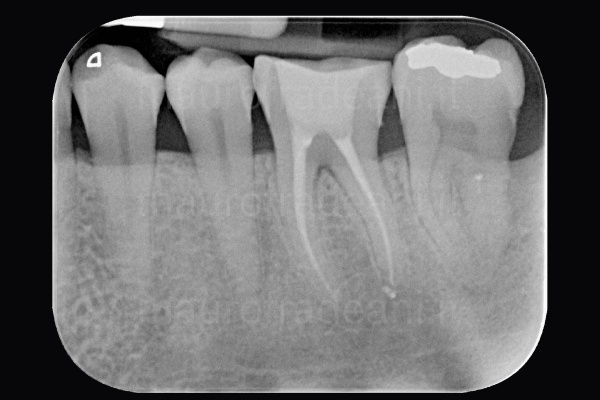

Vital tooth root canal treatment

1/2: The patient presents severe pain and a swollen cheek sensation; the X-ray shows an apical lesion (the dark shadow under the root) of the first lower left molar. A Root canal therapy to devitalize the tooth is necessary.

2/2: The X-ray taken 6 months after the surgery shows a marked improvement in the dark area under the root, which has now disappeared. The symptoms complained of by the patient have never occurred again.